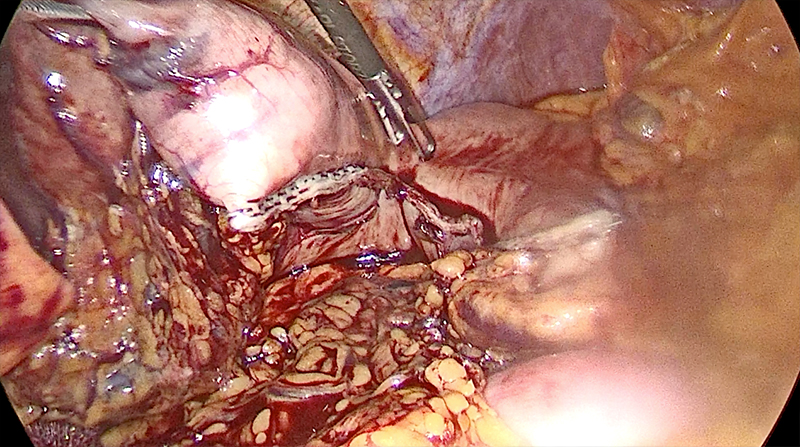

58 year old gentleman with recurrent abdominal pain, vomiting and weight loss was diagnosed with peptic ulcer disease and gastric outlet obstruction. He was operated and a laparoscopic (minimally invasive surgery) vagotomy and gastrectomy was done. The patient was discharged on 6th postoperative day & is completely cured of his problem since then.

Peptic ulcer disease requiring surgery due to various complications was a very common thing 30 years back. With advances in drugs available to control gastric acid, surgery has got a very little role now. Intermittent patients with acute complications like bleeding and chronic complications like obstruction are handled with endoscopic treatment followed by medicines. However once in a while surgeons will face peptic ulcer disease with complications like bleeding / obstruction which requires a surgery, perforation, cancer and poor response to medical line of treatment. Patient in the case mentioned also falls in this last group and needed a surgery (vagotomy – vagus nerve disconnection) to reduce secretion of acid secretion and a gastrectomy (removal of obstructed part of stomach involved by ulcer and scarring). The gastrointestinal continuity is reestablished by joining proximal small intestine with the remaining stomach. This surgery used to be done through a big incision earlier, however we perform it laparoscopically i.e. key hole surgery. This shortens & smoothens the recovery.